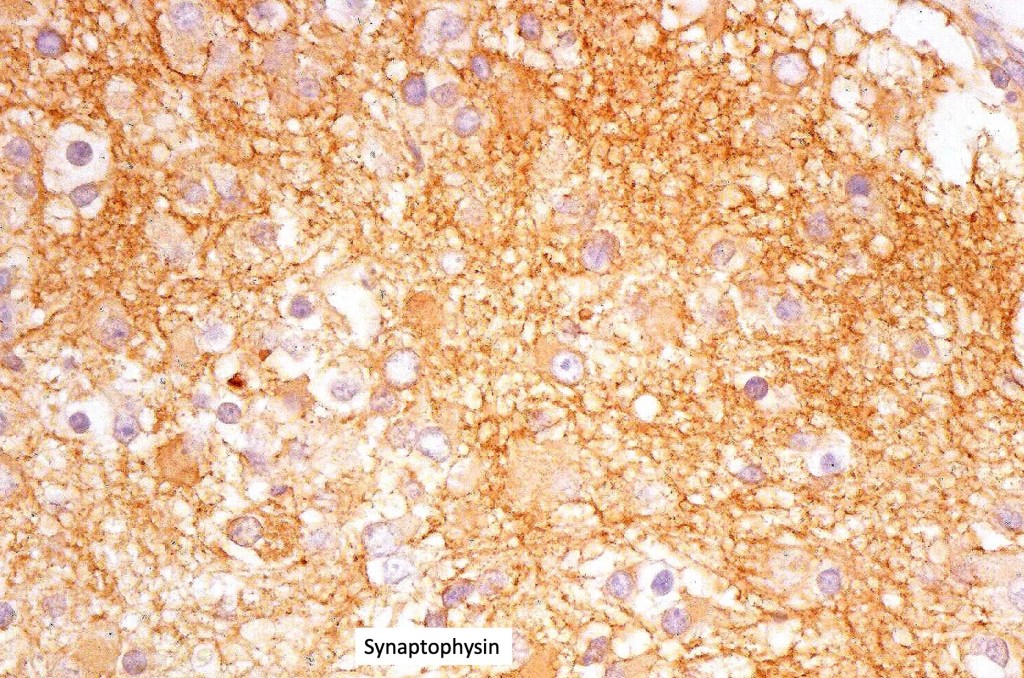

•Neuroendocrine